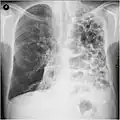

Outros exames

A realização de uma radiografia ao tórax e de um hemograma permitem excluir outras condições no momento do diagnóstico.[69] Os sinais característicos da DPOC observáveis em radiografia são pulmões sobre-expandidos, diafragma achatado e espaço retroesternal aumentado. Ao mesmo tempo, a radiografia permite excluir outras doenças pulmonares, como pneumonia, edema pulmonar ou pneumotórax.[70] Uma tomografia axial computorizada ao tórax permite mostrar a distribuição do enfisema pelos pulmões e pode ajudar a excluir outras doenças pulmonares.[18] No entanto, a não ser nos casos em que se planeie a realização de uma cirurgia, esta distribuição raramente influencia o tratamento.[18] Pode ainda ser realizada uma gasometria arterial para determinar a necessidade de oxigénio suplementar. Este exame é recomendado em pessoas com VEF1 inferior a 35% do previsto, com saturação periférica de oxigénio inferior a 92% e pessoas com sintomas de insuficiência cardíaca congestiva.[17] Em regiões do mundo onde é comum a deficiência de alfa-1 antitripsina, as pessoas com DPOC devem considerar a realização deste exame, sobretudo aquelas com idade inferior a 45 anos e em que o enfisema afeta a parte inferior dos pulmões.[17]